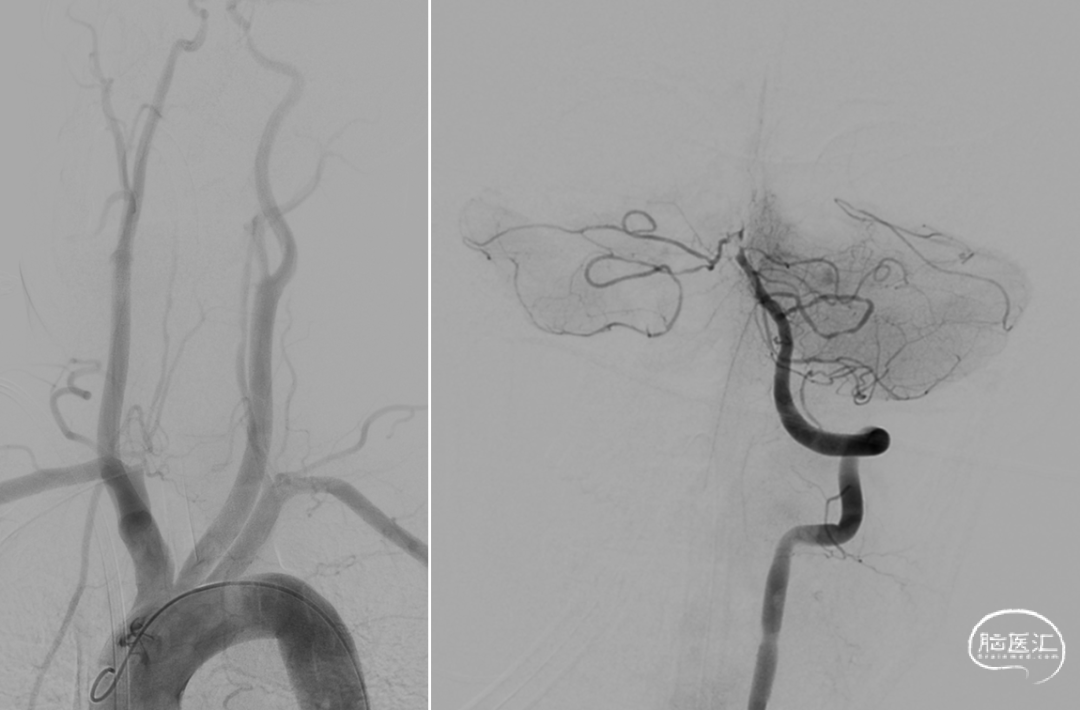

急诊DSA:Ⅱ型弓,基底动脉AICA以远未见显影。

加奇Tethys®中间导引导管到位,明确既往支架位置。但中间导管通过困难。

微导丝微导管通过闭塞段,在右侧大脑后动脉手推造影证实真腔,明确闭塞段,可见造影剂返流至基底动脉尖部,且证明闭塞确为支架内再狭窄导致闭塞。

释放加奇4.0mm*30mm Syphonet®取栓支架,可见支架通体显影。

第一次取栓后,血管未通,但明确支架内狭窄位置,交换引入头端塑形的300cm 0.014in微导丝,撤出微导管,沿微导丝引入2.0mm*15mm Sprinter球囊,扩张后狭窄明显减轻,但血栓掉落至右侧大脑后动脉起始部。

交换再次引入加奇4.0mm*30mm Syphonet®取栓支架并释放。

第二次拉栓后造影,血管再通,支架内再狭窄处理风险极高,且目前前向血流3级,对比造影时影像支架未有移位。